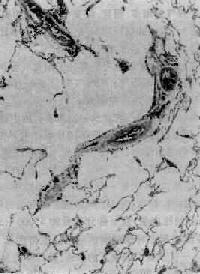

图9-12 腺泡中央型肺气肿

呼吸细支气管呈囊状扩张,伴行肺动脉(径80μm)管壁增厚,其分支内膜增厚,管腔极度狭窄